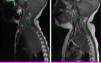

Todos los pacientes en los que se optó por quimioterapia presentaron una evolución favorable (fig. 1) excepto uno, que precisó una laminectomía. Todos fueron situaciones de debut.

Resonancia magnética (RM) de paciente con debut de neuroblastoma con compresión medular. a) Masa mediastínica superior izquierda de diámetro 7 x 5 x 9 cm que comprime la médula ósea desde nivel C7-T1 hasta T3-T4. b) RM tras administración de ciclo etopósido-carboplatino: masa 5 x 5 x 8 cm, cuyo componente intracanal ha disminuido, observando menos efecto masa sobre el cordón medular, que recobra tanto su grosor como su intensidad de señal.